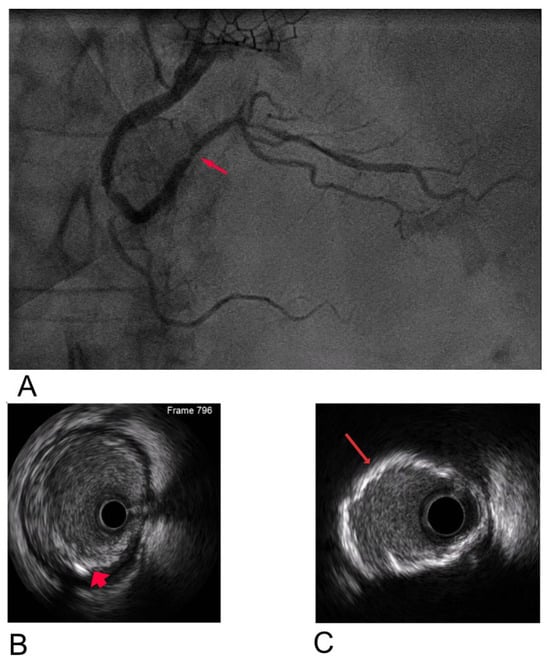

To address these challenges, adjunctive imaging modalities have been adapted to enable ultra-low contrast PCI. Intravascular ultrasound (IVUS) provides detailed cross-sectional images without reliance on contrast media (Figure 1) and is recommended in complex interventions [5,6]. OCT provides high-resolution plaque characterisation and stent assessment (Figure 2), but requires flushing, typically with contrast media; however, substitutes such as low-molecular-weight dextran and heparinised saline have shown promise as alternatives [51,52,53,54]. DCR software overlays a live coronary roadmap onto the fluoroscopic image, enabling navigation of coronary tools and stent delivery without repeated contrast injections (Figure 3) [7,55]. While these modalities provide valuable anatomical information, they remain dependent on fluoroscopic platforms and do not eliminate contrast use entirely, highlighting the potential role for complementary navigation technologies such as EAMS.

Figure 1. Multi-plane illustration of right coronary artery (RCA) assessment: (A) Coronary angiogram showing multiple areas of stenosis, with one marked by an arrow. (B) IVUS image demonstrating a fibrocalcific plaque in the mid RCA (arrow). (C) IVUS image showing a 360° arc of calcium in the RCA, with the arrow highlighting the calcification.